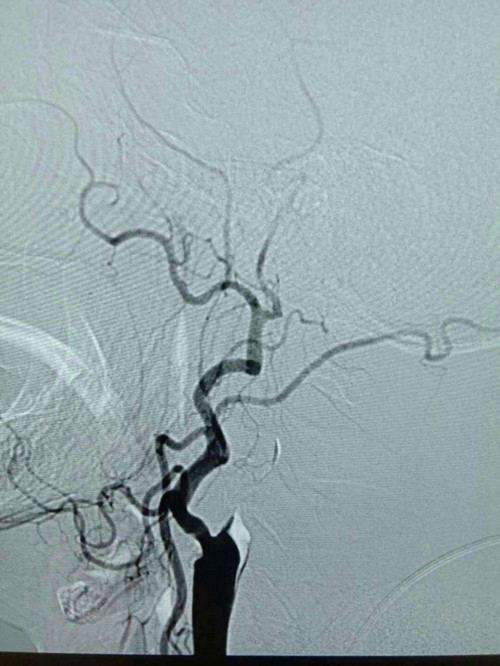

由于患者发病时间为3小时,神经内科医生立即通知介入中心小组成员,同时与家属交代病情,经家属同意,在导管室为患者进行股动脉穿刺。10分钟内穿刺成功,20分钟造影完成。造影结果显示右侧颈内动脉起始处闭塞,无良好代偿。医生给予微导管造影,判断闭塞段长度为15mm,缓慢注射阿替普酶5mg,血管内血栓逐渐溶解。因前段闭塞,仍未见有效血流,与家属再次沟通,决定开通闭塞的右侧颈内动脉。经过紧张、迅速的介入治疗,球囊扩张血管完成,闭塞段开通,残余狭窄85%,前向血流维持2a级,手术顺利完成。术后复查头CT未见出血,狭窄处择期支架成形治疗。术后患者神志清晰,言语较前流利,左侧肢体肌力由0级变为5级弱。